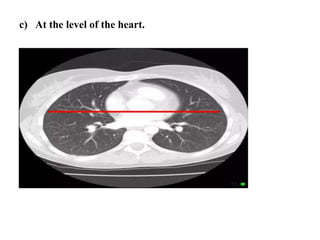

c) At the level of the heart.

• At the level of the heart.